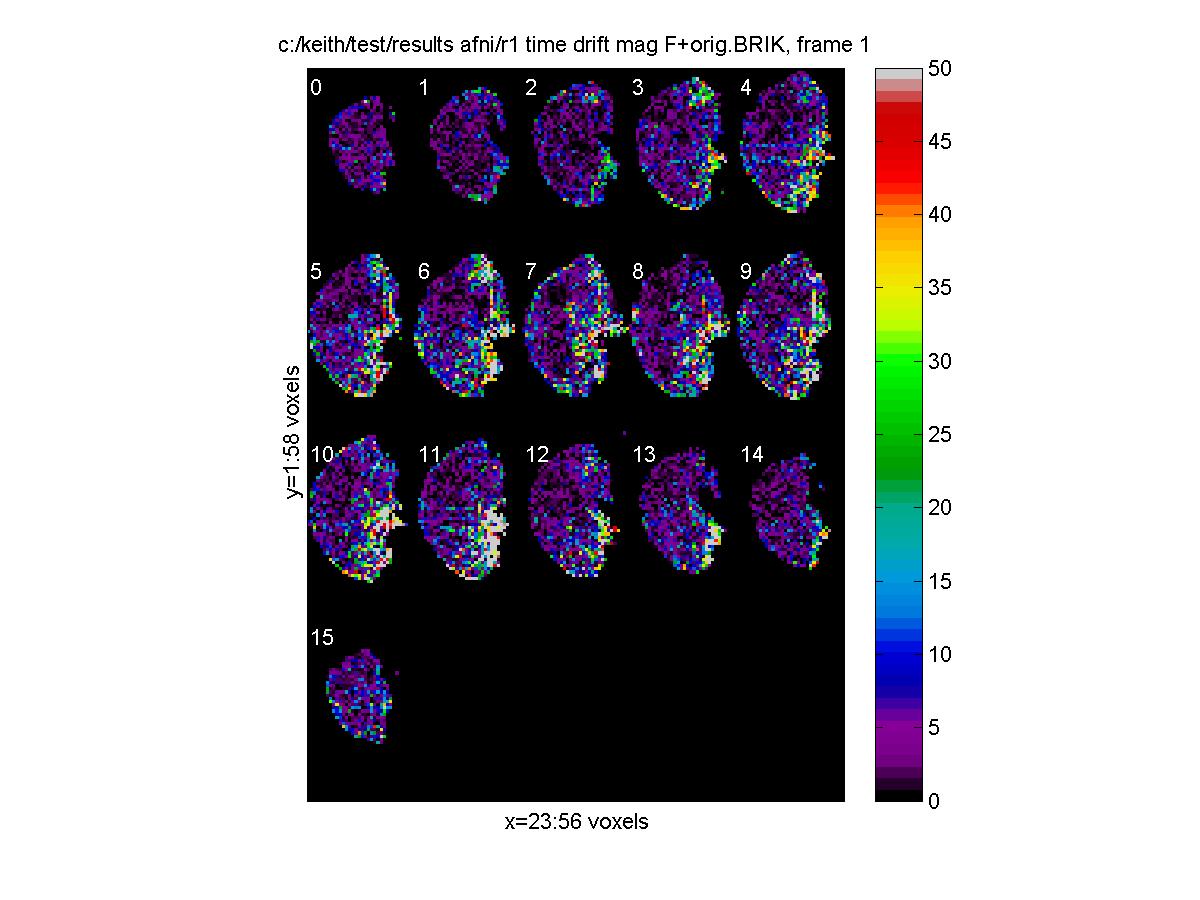

F-tests

F-tests should only be used when we are interested in any linear combination of the contrasts. For example, an F-test would be appropriate for detecting regions with high polynomial drift, since we would be interested in either a linear, quadratic or cubic trend, or any linear combination of these. The drift terms appear after the regressor terms, in the order constant, linear, quadratic, cubic etc. So to test for a drift, use the contrast contrast.T=[0 1 0 0; 0 0 1 0; 0 0 0 1] which_stats='_mag_F'; output_file_base='c:/keith/test/results_afni/r1_time_drift'; fmrilm(input_file,output_file_base,X_cache,contrast,exclude,which_stats,cor_file); fwhm_data = 6.6393 fwhm_cor = 6.6168 df = resid: 58 cor: 299 t: [43 44 45] F: [3 44] clf; view_slices('c:/keith/test/results_afni/r1_time_drift_mag_F+orig.BRIK',mask_file,[],0:15,1,[0 50]); [Click to enlarge image]

The F statistics for testing for drift has df.F = 3 44. Note that we can use stat_threshold to find the threshold for significant drift (see later).